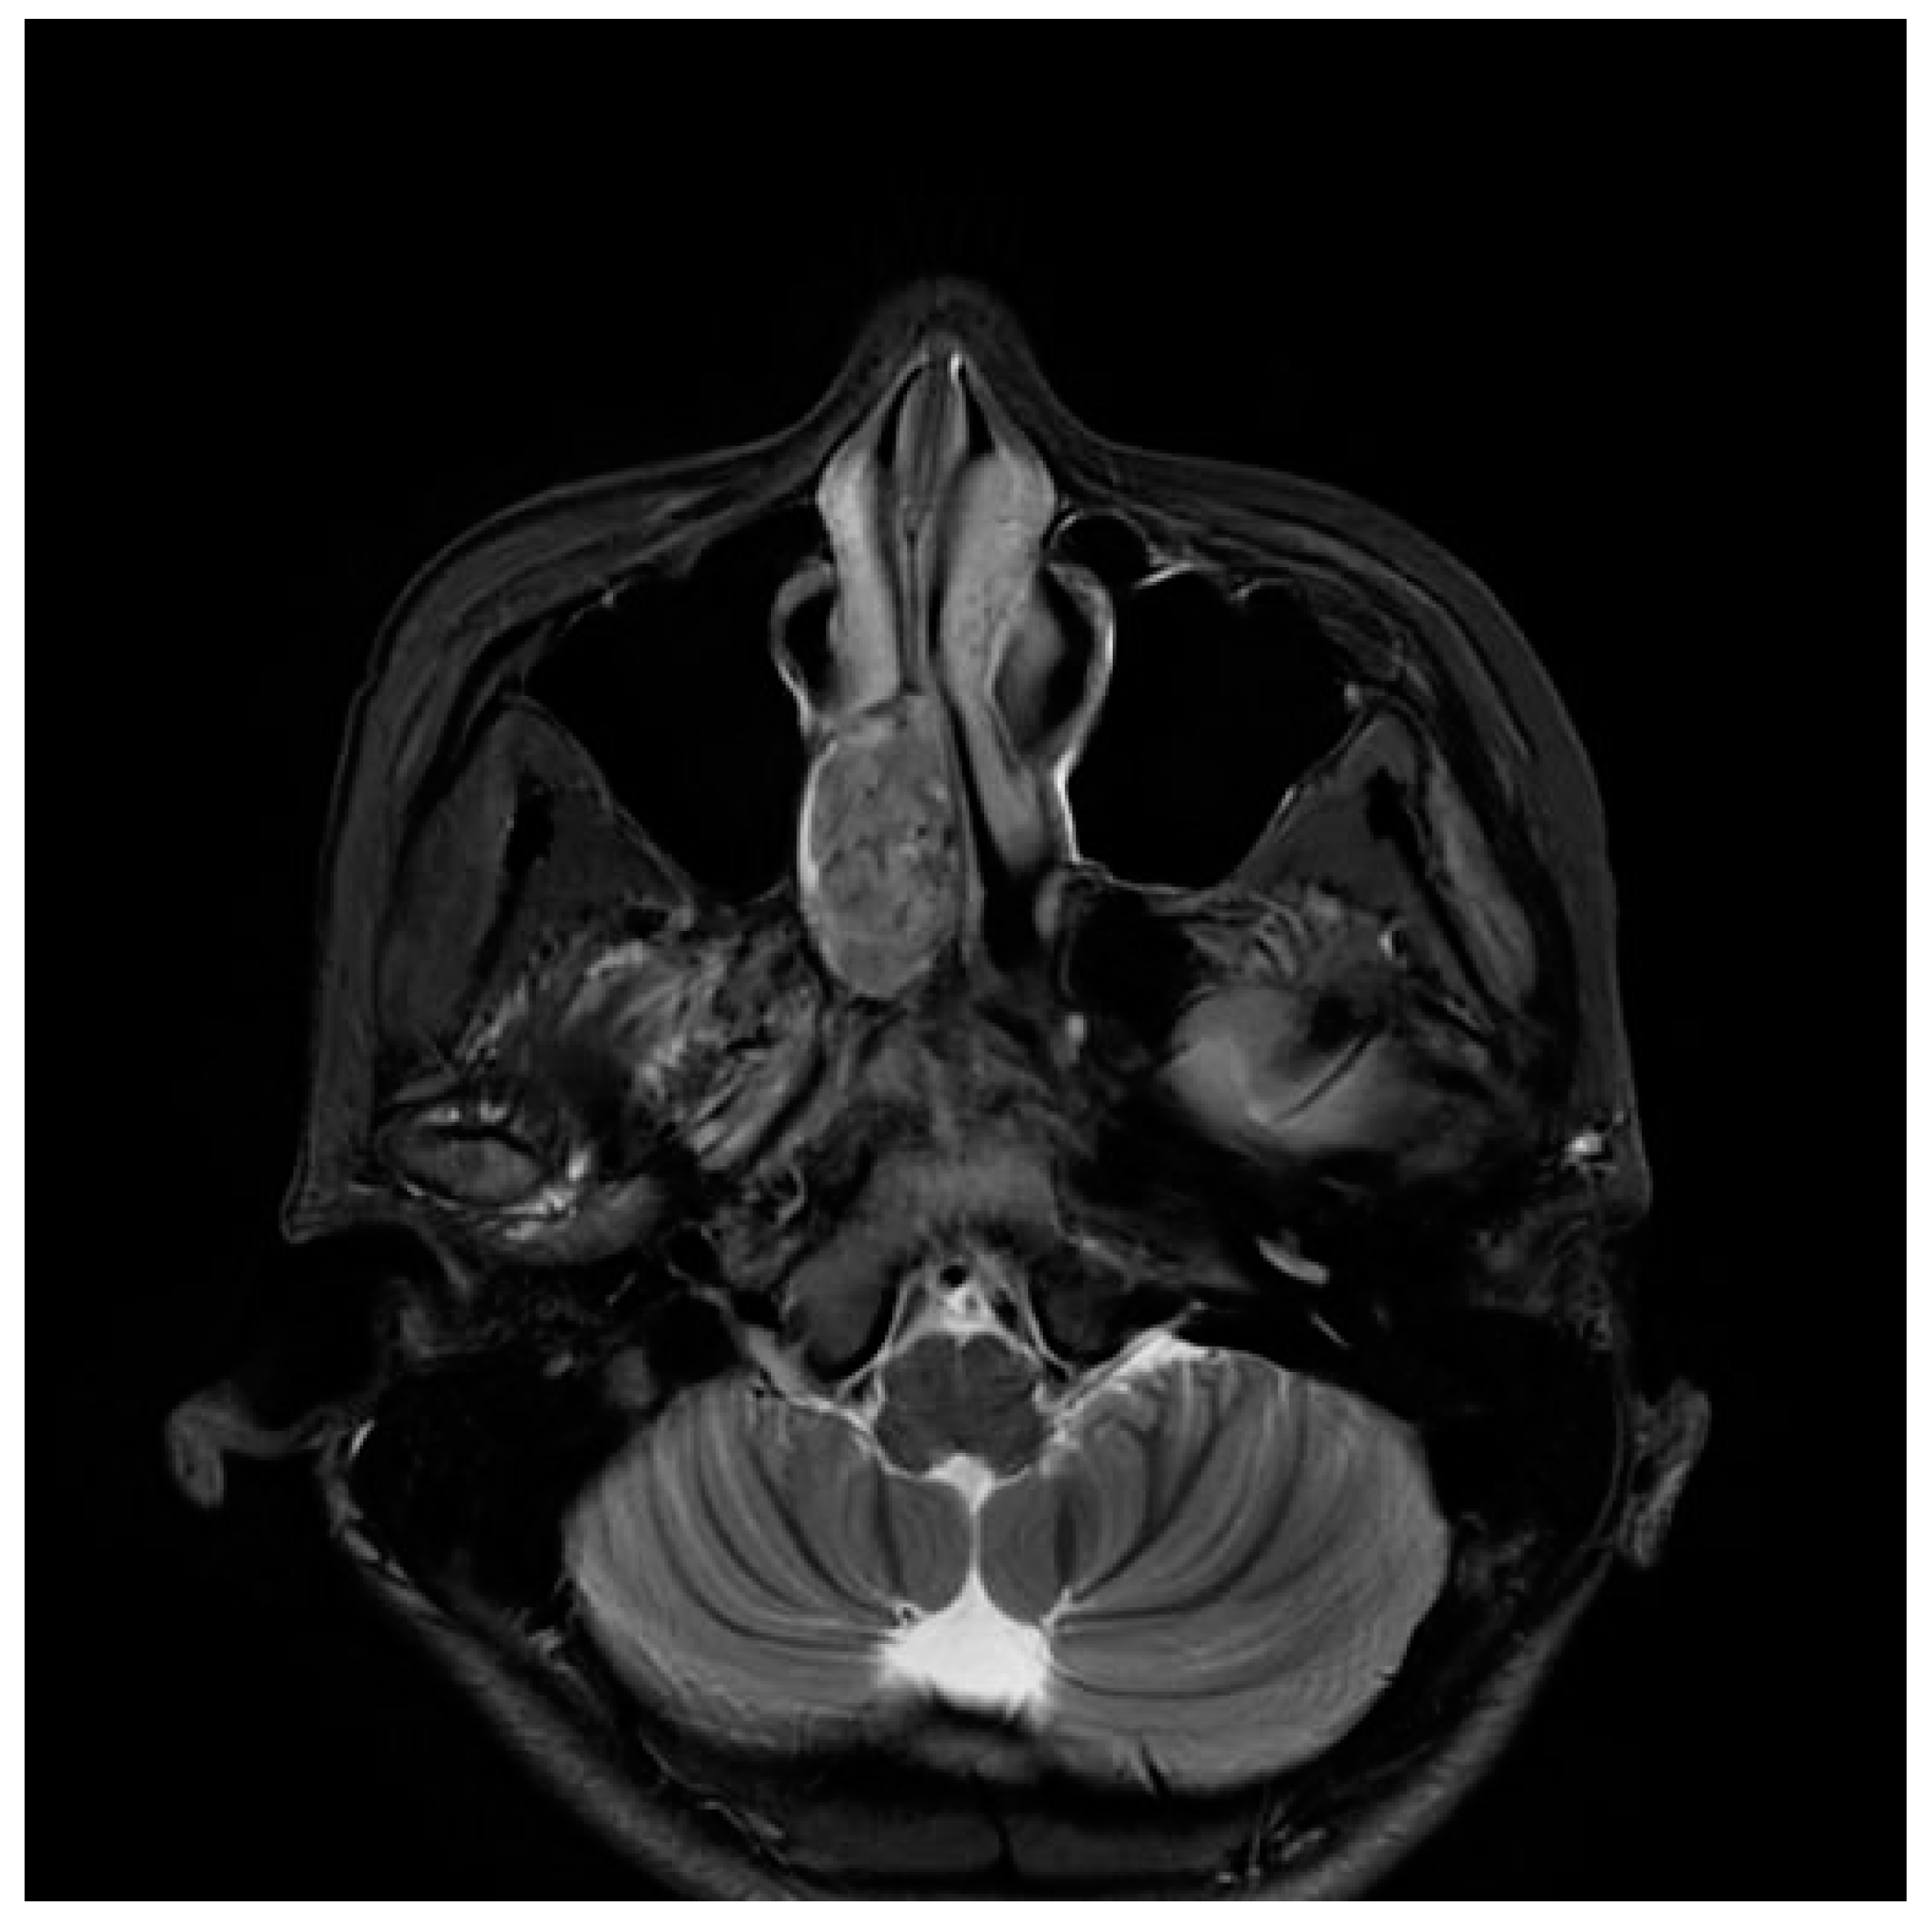

A 17-year-old female patient presented with a 2-year history of right nasal obstruction. She was currently taking medication for attention deficit hyperactivity disorder (ADHD) and depression. She had been treated for precocious puberty seven years ago. She had a history of traumatic cerebral hemorrhage 14 years ago. In addition, she had a family history of pharyngeal cancer in her grandfather. Nasopharyngoscopy revealed a polypoid mass in the right posterior nasal cavity (Figure 1). Paranasal sinus magnetic resonance imaging (PNS MRI) demonstrated a well-defined enhancing mass at the right nasal cavity, involving middle and inferior meatus, measuring 3x3x1.6 cm in dimensions. The mass exhibited medium signal intensity on T2 weighted image (Figure 2). These images were interpreted as juvenile nasopharyngeal angiofibroma.

Figure 2. PNS MRI showed a nasal cavity mass approximately 3 cm in size, well-circumscribed, and with medium signal intensity on T2-weighted image axial view.